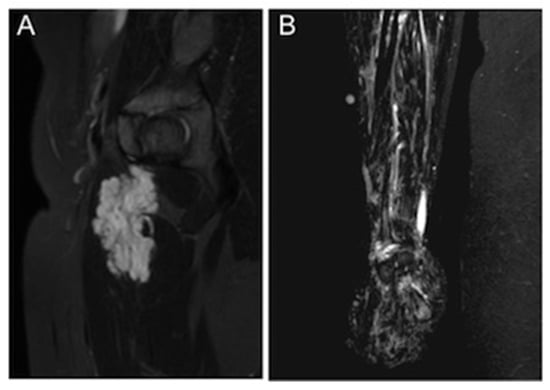

We determined the size, location, affected tissue planes, morphological appearance, and presence of phleboliths of each VM based on the MRI studies. Because VMs are irregularly shaped and often diffusely infiltrate normal tissues, exact dimensions could not be obtained. We measured the greatest diameter in any of the three planes and graded it as small (<5 cm), medium (5–10 cm), wide (10–25 cm), or extensive (>25 cm). Lesion location was defined as head/neck, trunk, or extremities. According to the affected tissue planes, the depth of the lesion was categorized into three groups: (1) superficial lesions confined to subcutaneous fat, (2) lesions with an intramuscular, -osseal, or -articular component, and (3) deep lesions with an intra-abdominal, retroperitoneal, or intra-thoracic component. We divided the malformations into two categories by morphology: (A) discrete, relatively well-demarcated malformations and (B) diffuse, phlebectatic malformations (Figure 1). Phleboliths were defined as small intraluminal foci of signal-voids, visible both in T1- and T2-weighted sequences, consistent with calcifications.

Figure 1. An example of the two different morphological appearances of VMs in MRI. (A) A discrete and well-demarcated VM in the thigh muscles. (B) A diffuse VM of the right forearm.

Figure 2. Axial (A) and coronal (B) T2-weighted MR images of an extensive VM affecting the retroperitoneum and spinal muscles and dislocating the bowel and the right kidney to the left.